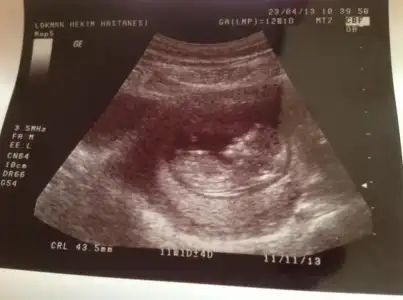

meraba benim bebişminde cinsiyetini tahmin edermisiniz be erkek hissediyorum ama drum bişey demedi henüz bu görüntü 11+5 :16:: $2013-04-26-375.webp $2013-04-26-374.webp